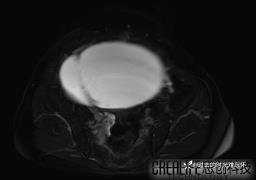

腹大能容5000液;术后腹部好轻松。妙手回春有结果。公布结果。

患者性别:女

患者年龄:65岁

主诉: 发现腹部隆起半年余。无其他明显不适。

浆液性囊腺瘤 (22)